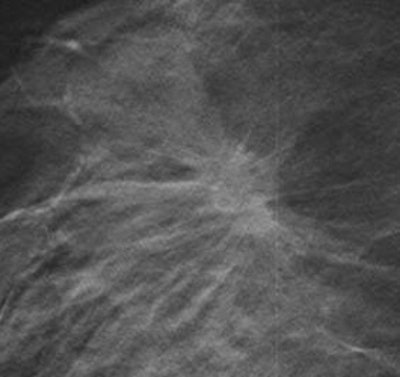

With tomosynthesis, low-dose images are obtained over a limited arc, and the projections are mathematically reconstructed into a series of sections with the hope that specificity and sensitivity will be improved. Initial work using tomosynthesis as an add-on to conventional 2D mammography suggested the potential for substantial improvements in specificity, the authors noted. They compared the diagnostic accuracy of 2D digital mammography with that of two-view (mediolateral and craniocaudal) and single-view (mediolateral oblique) tomosynthesis in an observer study involving two institutions: Cambridge and Capio St Göran's Hospital in Stockholm.

For diagnostic accuracy, 2D mammography performed significantly worse than two-view tomosynthesis (average area under receiver operating characteristic curve [AUC] = 0.772 for 2D, AUC = 0.851 for tomosynthesis; p = 0.021). The researchers found significant differences for masses and microcalcification (p = 0.037 and 0.049, respectively). The difference in AUC between the two modalities was significant only for the five readers with the least amount of experience (p = 0.03 versus p = 0.25 for readers with 10 or more years of experience). No significant difference was seen in reader performance when 2D mammography was compared with single-view tomosynthesis.